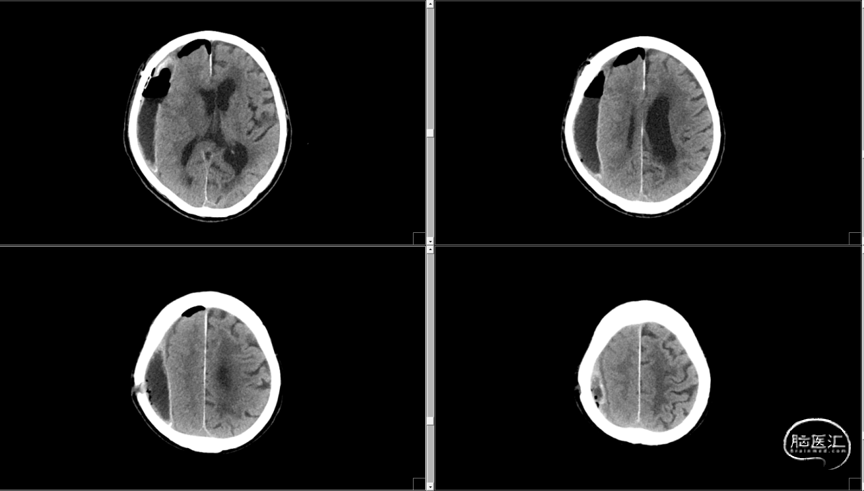

初步诊断:1. 右侧额颞顶慢性硬膜下血肿;2. 冠状动脉粥样硬化性心脏病术后;3. 高血压病2级(极高危)

术前CT